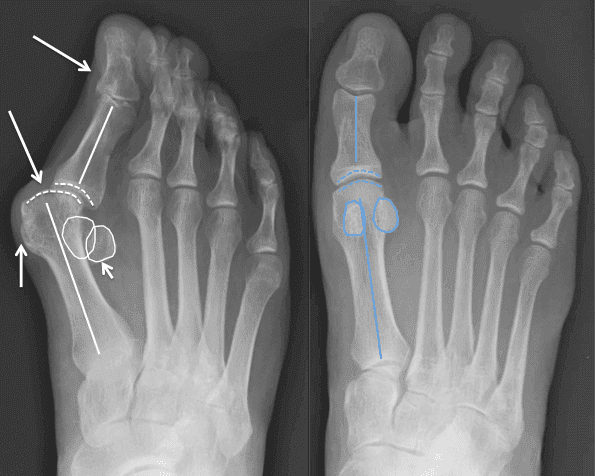

Przez długi czas odczuwałam silny ból stóp. W rezultacie wystąpiły trudności w poruszaniu się. Poszłam do specjalisty i zdiagnozowano u mnie paluch koślawy. Zaproponowali mi operację stóp, ale za bardzo bałam się zabiegu. Na szczęście poznałam Andrzeja i zaczęłam używać ReumoMax Complex. Po trzech dniach ból całkowicie ustąpił, a tydzień później chodziłem bez bólu i zaczęłam uprawiać nordic walking. Zdjęcie pokazuje moje postępy."

A oto wyniki ReumoMax Complex po 10 dniach:

Damian: "Miałem problemy związane ze stopą. Niczego nie brałem ... Poszedłem do specjalisty, stosowałem maści i środki ludowe... Nic nie pomogło. Zaufałem Andrzejowi, wziąłem udział w eksperymencie. Po 2 tygodniach po problemie nie było śladu! Oto mój wynik. Dziękuję Andrzejowi".